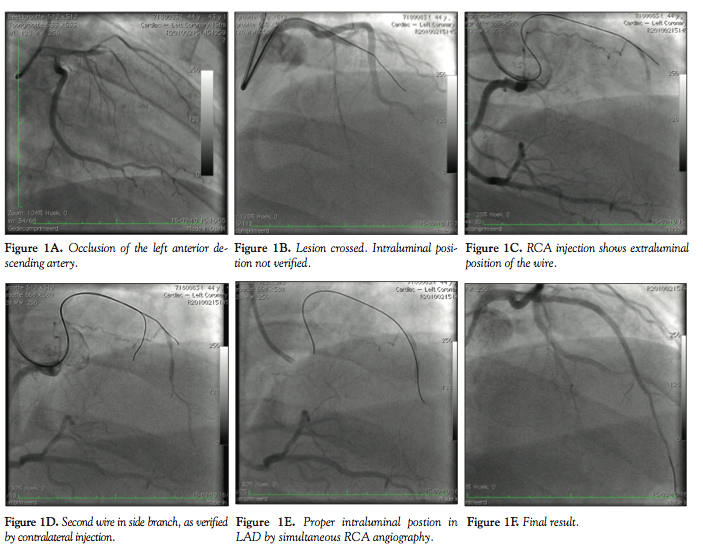

Patient #1. A 44-year-old male patient was referred for PCI of a CTO of the left anterior

descending (LAD) artery because of stable angina pectoris. The LAD was proximally occluded (Figure 1A) and there was good retrograde filling via collaterals from the right coronary artery (RCA). PCI was performed via the right radial approach (RRA) with a 6 Fr Kimny guide (Boston Scientific). An Asahi Miracle 3 guidewire was advanced to a point distal to the occlusion. However, intraluminal position was not evident (Figure 1B). By carefully rotating the catheter to the RCA, the RCA could be cannulated and filmed, which showed extraluminal position of the wire (Figure 1C). A second Asahi Miracle 3 wire was advanced after recannulation of the left coronary artery. By the same technique, it became evident that the tip of this wire was positioned in a small side branch (Figure 1D). A third attempt with an Asahi Miracle 6 wire resulted in an intraluminal position of the wire (Figure 1E), after which predilatation was performed and 3 drug-eluting stents were placed. The final result was good (Figure 1F).